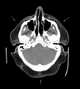

Benign symmetric lipomatosis is a skin condition characterized by extensive symmetric fat deposits in the head, neck, and shoulder girdle area. The German surgeon Otto Wilhelm Madelung was the first to give a detailed description of the disorder. [Source: Wikipedia ]

Fatty parapharyngeal space lesion

Fatty tumor of the neck